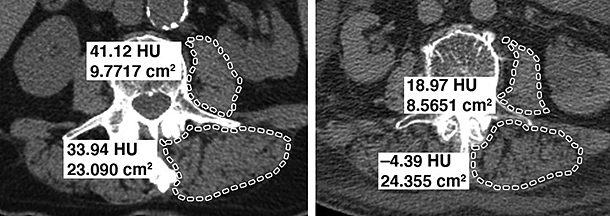

Measurements for osteoporosis in the spine are generally taken at the specific thresholds at the L1 level. If the vertebral body has an attenuation of 90 HU or less, it is considered to be osteoporosis; conversely, attenuation of more than 160 HU essentially rules out osteoporosis.7-8 Fig. 1 demonstrates two different patients: one with normal bone density and the other with osteoporosis.

CT-derived thresholds for diagnosing low muscle mass and attenuation have been established; the current diagnostic threshold is 30 HU for both the psoas and paraspinal muscles, so any measurement lower than 30 HU is indicative of myosteatosis. (Fig. 2)